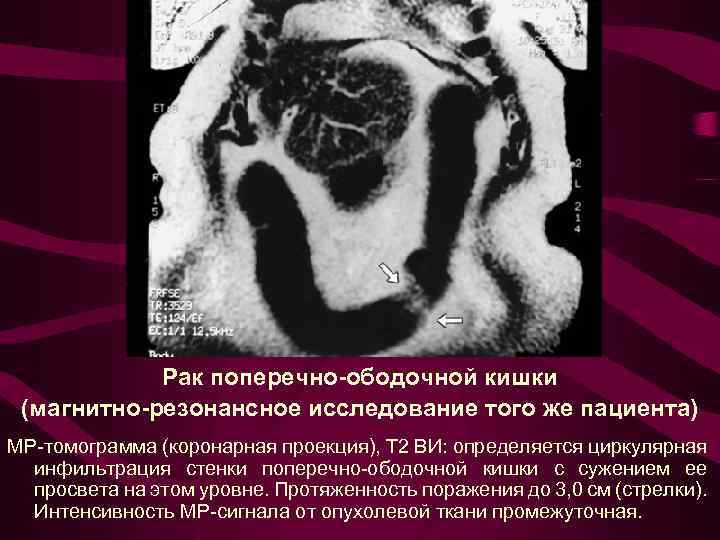

Рак поперечно-ободочной кишки (магнитно-резонансное исследование того же пациента) МР-томограмма (коронарная проекция), Т 2 ВИ: определяется циркулярная инфильтрация стенки поперечно-ободочной кишки с сужением ее просвета на этом уровне. Протяженность поражения до 3, 0 см (стрелки). Интенсивность МР-сигнала от опухолевой ткани промежуточная.